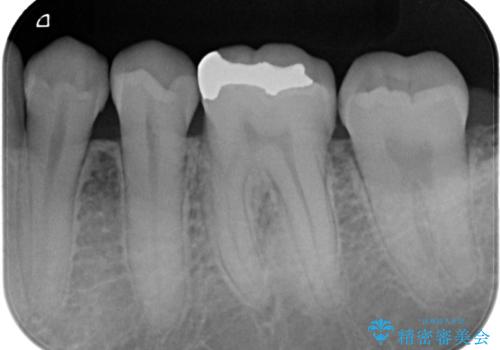

精度の良いインレーを製作するために、シリコーンにて型どりしました。

また確実な接着操作を行うために、インレーを接着する際にはラバーダム防湿を行いました。

- 21万円(税込) ※3歯費用は治療当時の料金となります